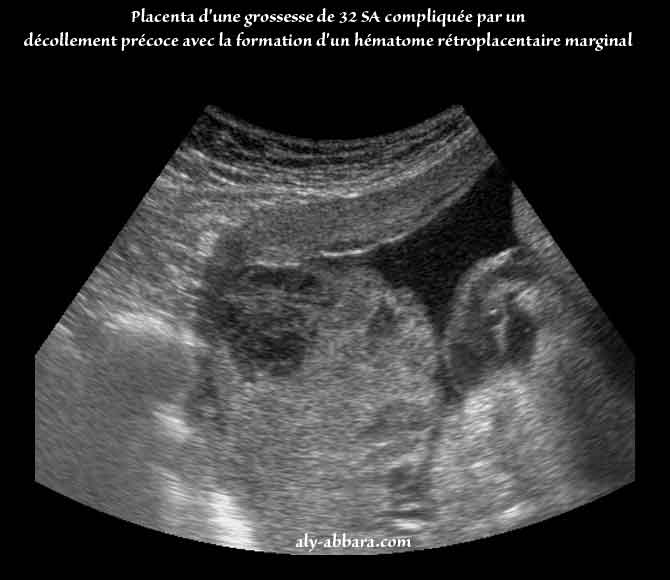

Forum Attendre bb - auFeminin Hematome decidual? Les mamans avec dcollementhmatome durant la grossesse - Page. Bonjour toutes je suis enceinte de 5sa5(selon gygy) et vendredi il a trouv l echo un hematome decidual.Jss arrete 15j et repos, il. Dcollement placentaire - Dcollement du placenta en cours de. Hmatome dcidual marginal pdia Un hmatome dcidual marginal est une complication de la grossesse survenant lorsqu une portion marginale du placenta se dcolle, ce qui entrane un.

J ai eu un cho de suivi pour le dcollement et l hmatome. Il peut correspondre un hmatome dcidual marginal ou un hmatome rtro- placentaire, lequel est une urgence obsttricale absolue. L hmatome rtroplacentaire doit tre distingu de l hmatome dcidual marginal qui correspond la dchirure d une veine utro-placentaire marginale crant. Hmorragie gnitale - SMART fiches fvr. en Midi Py on trouverait des plugs dans les vide greniers? 20: dcouvrez les plus beaux modles de carrs dgrads du moment.

Hmatome dcidual marginal pdia